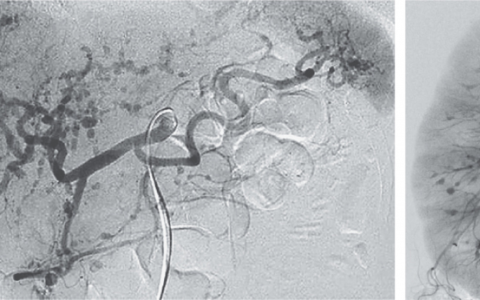

A 96-year-old woman presented to the emergency department with a 1-day history of pleuritic chest pain 4 days after a single-chamber transvenous pacemaker had been implanted. A chest radiograph and computed tomographic scan of the chest showed the tip of the right ventricular lead in the left pleural space. What rhythm does the electrocardiogram show?

心电图显示完全性心脏传导阻滞,心房频率为84次/分,交界区逸出,右束支传导阻滞,心率为42次/分,以及无心室夺获的起搏棘波。诊断为起搏器导线脱位伴心脏穿孔。紧急进行了经皮导线翻修,患者在就诊后3日出院回家。